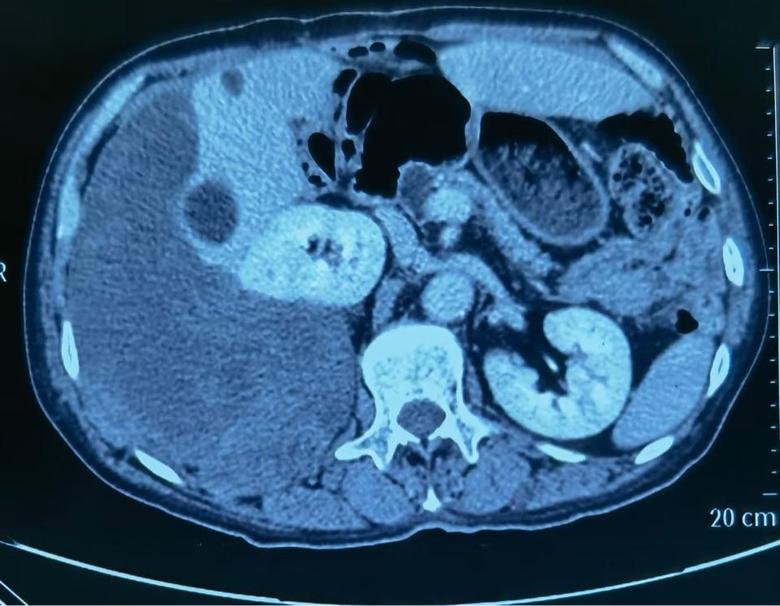

病例2

今日下午,2例巨大腹膜后肿瘤手术在我科顺利开展,腹膜后肿瘤发病率低,手术难度大,手术风险大,国内开展相关手术单位为数不多,我院腹膜后肿瘤手术量连续数年位居国内前列,在腹膜后肿瘤领域团队具有丰富经验,巨大腹膜后肿瘤手术开展,表明该类手术在我院已经成为常态。并且将继续保持国内在领先水平。